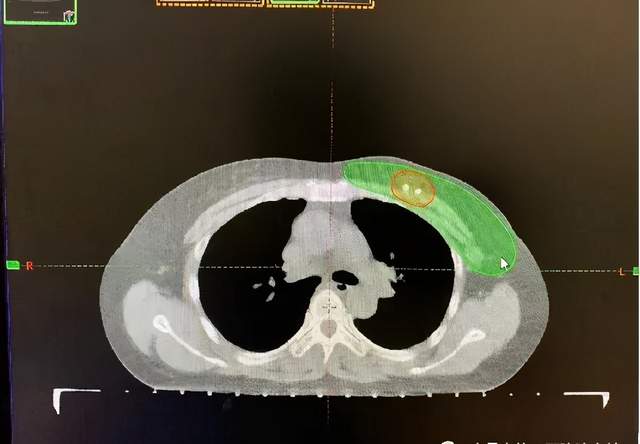

乳腺癌术后辅助放疗

保乳术后放疗